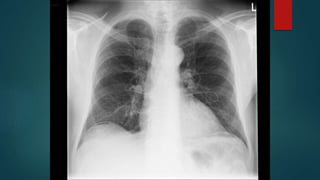

Breathing

Low tidal volumes

Modest fluid

Breathing Low tidal volumes Modestfluid resuscitation Ventilation with Lower Tidal Volumes as Compared with Traditional Tidal Volumes for ALI and the ARDS. N Enlg J Med. 2000; 342:1301-1308. Comparison of Two Fluid-management Strategies in Acute Lung Injury. N Enlg J Med. 2006 Jun;354(24):2564-75. two

• #11 Low tidal volumes has been well established. May have to tolerate a degree of resp acidosis. May need more PEEP also. 861 patients in initial study - no mortality benefit but less time ventilated and in ICU. Later small studies show a 28-day mortality benefit